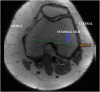

Fig. 2

Axial Magnetic Resonance Imaging (MRI) image Showing method of measurement of femoral medio-lateral dimension (MLD).

Fig. 3

Axial Magnetic Resonance Imaging (MRI) image Showing method of measurement of femoral antero-posterior dimension (APD).

Methods: The knee MRI data of 68 patients (43 males and 25 females) were studied. Measurement of PT-FCL distance was done in sagittal proton density fat-saturated (PDFS) sequence images. The femoral MLD and APD were measured in axial PDFS sequence images. The mean of each parameter was calculated and analyzed. To identify inter-observer agreement, we calculated Intra-Class Correlation Coefficient (ICC) for each parameter.

Results: The mean PT-FCL distance was 16.85 ± 1.55 mm (range 12.9-21.2 mm). In our observation, PT always inserts anteriorly and distally to FCL insertion on the lateral femoral condyle. The mean MLD was 78.74 ± 5.84 mm (range 65-90 mm). The Mean APD of the lateral femoral condyle was 60.47 ± 4.00 mm (range 52.5-69.5 mm). The difference between the mean values of all the above parameters in both genders was statistically significant (p-value <0.05). Inter-observer agreement was very good for measurement of PT-FCL distance (ICC 0.96), MLD (ICC 0.98) and APD (ICC 0.97).